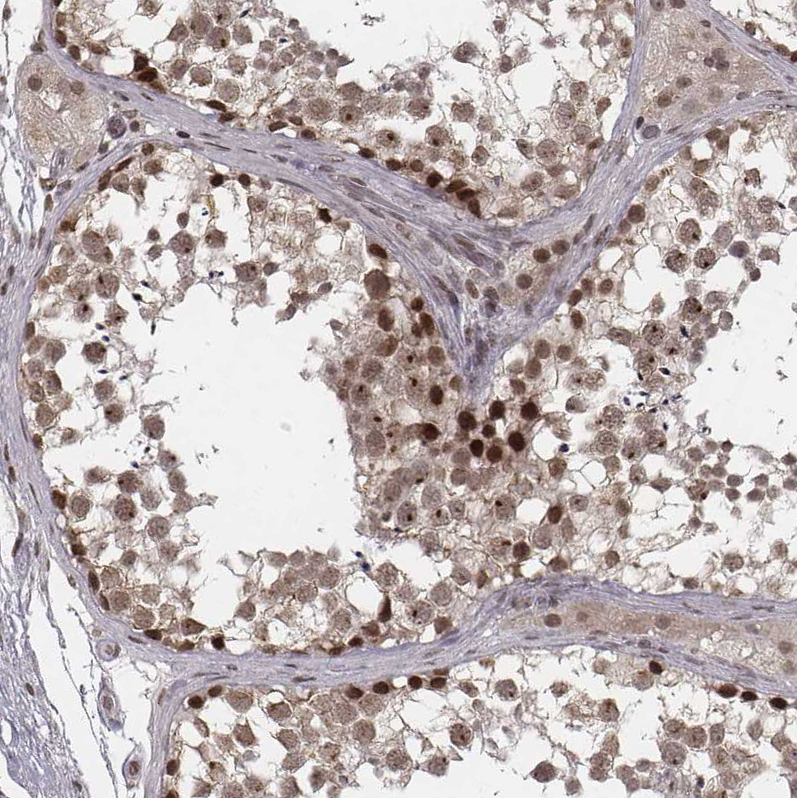

Immunohistochemical staining of human testis shows moderate to strong nuclear positivity in cells in seminiferous ducts.